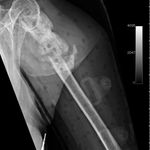

Some time in late May 2010, she presented with movement of the fracture site and was noted that the central area of healing had broken down and was thought that she had a deep infection. She was taken back to theater in mid June 2010 when operation showed that there was no pus. Multiple samples of the fracture site were taken and an external fixator applied with compression of the fragments. Following that, the cultures taken from the wounds showed no growth and no organisms and a biopsy showed no sign of any malignancy or abnormal cells. The fixator became loose and eventually had to be removed. This was done in July 2010 and she was discovered to be going onto a hypertrophic nonunion. Low dose ultrasound treatment of the fracture site was tried to help stimulate healing over the course of a few months but the non union persisted.

She was advised of the need to do some sort of stabilization which is necessary since the use of low-dose ultrasound has not helped in the healing process. She was unwilling to have any further operative intervention and sought further options. Eventually, she agreed to a fourth procedure of intra-medullary nail stabilization of the fracture and had this carried out in April 2011. An intramedullary nail was inserted in an antegrade manner and she has since gone on to heal the fracture site completely and has regained most of the function of the upper limb with no pain.